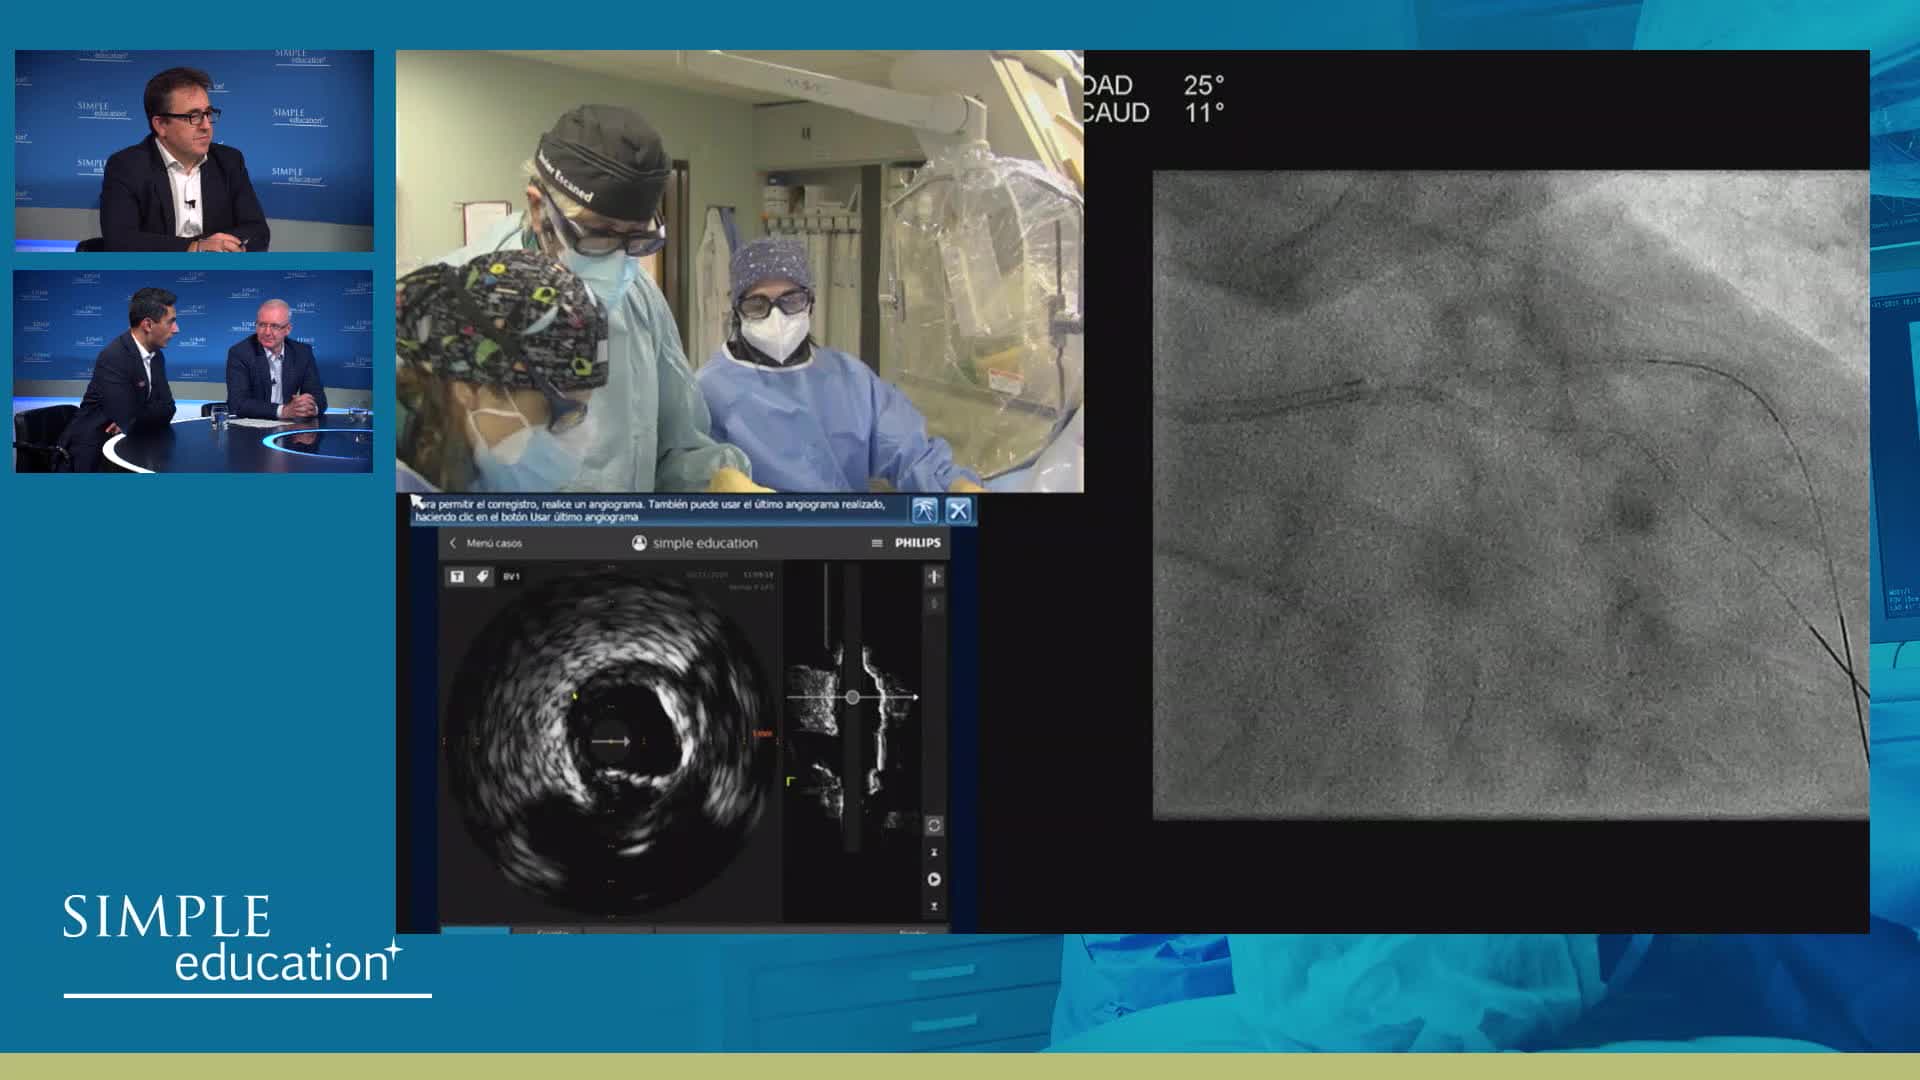

Advances in Co-registration, Coronary Physiology & Intra Coronary Imaging - April 2024 Day One

Advances in Co-registration, Coronary Physiology & Intra Coronary Imaging - April 2024 Day Two

Advances in Co-registration, Coronary Physiology & Intra Coronary Imaging - November 2023 Day One

Advances in Co-registration, Coronary Physiology & Intra Coronary Imaging - November 2023 Day Two

Advances in Co-registration, Coronary Physiology & Intra Coronary Imaging - March 2022 Day One

Advances in Co-registration, Coronary Physiology & Intra Coronary Imaging - March 2022 Day Two